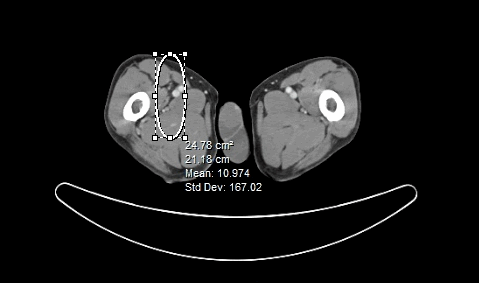

The FreeHand ROI is used by holding down the mouse button and drawing on the image by free hand. Once the mouse button is released, the beginning and ending points of the region are linked by a straight line in order to close off the region. The following image contains one of each of the four possible ROI annotations.

Each annotation display information on the area of the ROI and the Mean and Standard Deviation values of the pixel intensities.